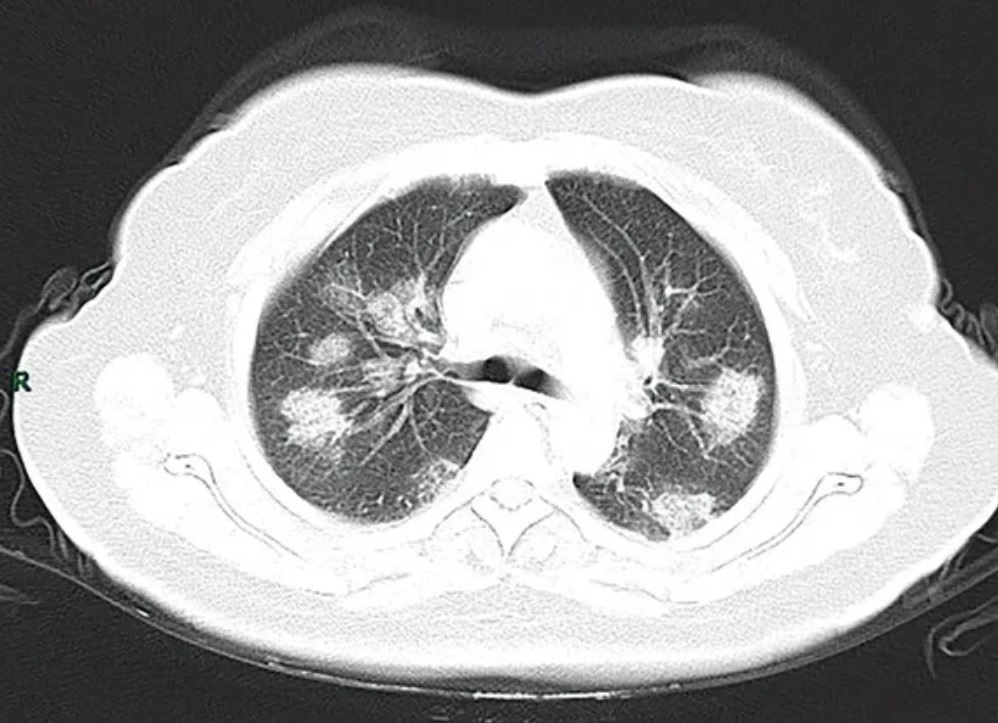

6. 2. 영상법

코로나19에 감염된 환자들을 방사선촬영과 컴퓨터단층촬영(CT)를 통해 확인하면 간유리음영이 비대칭적으로 관찰되는 것을 볼 수 있다. 이런 현상은 아데노바이러스 감염에서도 나타나기 때문에 영상법만으로 증상의 원인이 코로나19라는 것을 확인하기는 불가능하다. 그럼에도 불구하고 영상법을 통한 검사 방식이 더 빠르고 민감하다는 사실이 알려져 있다.